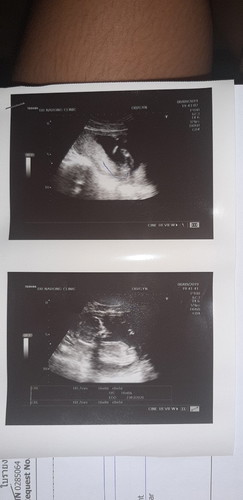

ผู้ชายหรือหญิงค่ะ แต่หมอบอกหญิง90% แต่แฟนบอกบอกดูไม่ออกค่ะ